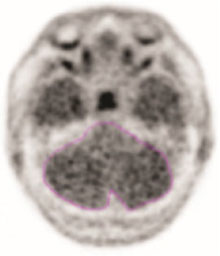

• To evaluate the temporal lobes, subdivide them into four quadrants by placing the horizontal crosshair immediately posterior to the brainstem nuclei and then scrolling inferiorly to place the vertical crosshair through the widest portion of the temporal pole, thus obtaining the anterolateral temporal (ALT), anterior mesial temporal (AMT), posterolateral temporal (PLT) and posterior mesial temporal (PMT) quadrants. See Figure 2 for an example (the left and right image panels show the same scan in two different color scales).

Figure 2: Temporal Lobe Quadrants